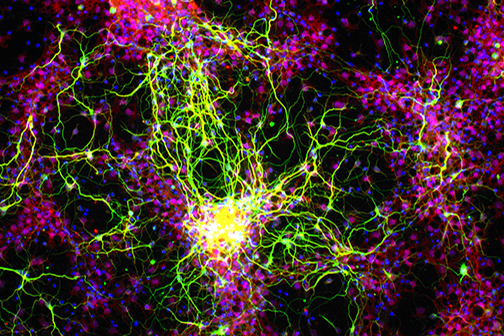

Scientists at LSU Health New Orleans’ Neuroscience Center of Excellence, led by Nicolas Bazan, MD, PhD, Boyd Professor and Director, have identified a new mechanism that regulates a protein key for cell survival. It appears to protect against the excessive oxidative stress that precedes the development of neurodegenerative diseases of the brain and eye. More

A study led by Nicolas Bazan, MD, PhD, Director of the LSU Health New Orleans Neuroscience Center, pinpointed which cells within specific areas of the brain are involved in post-stroke response and found that the delivery of precursors of Elovanoids, a class of molecules that synchronize cell-to-cell communication and neuroinflammation/immune activity in response to injury, improved neurological deficit in an experimental model of ischemic stroke. More

LSU Health New Orleans Study Identifies a Potential New Approach to PTSD Treatment

LSU Health New Orleans Researchers Discover a Key Failure in AMD that May Lead to Progression & Vision Loss

LSU Health New Orleans Researchers Discover Potential New Rx Strategy for Ischemic Stroke